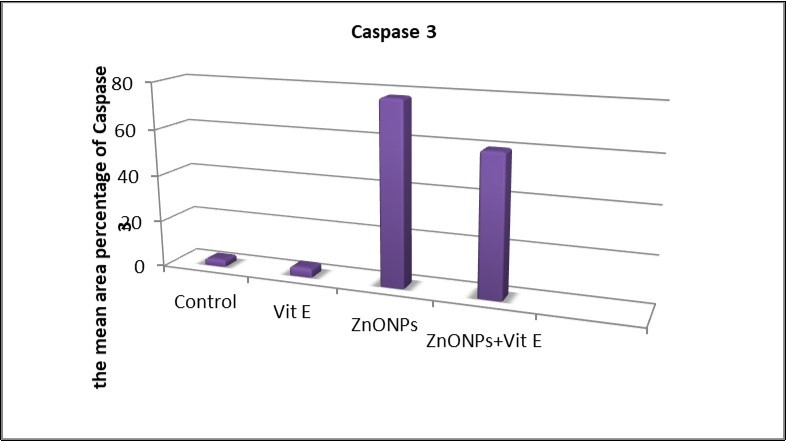

The results of the present study showed a very highly significant increase (P<0.001) in the number of hepatocytes with positive immune reaction for Caspase 3 in the ZnONPs-treated group when compared with other groups (Figure 12).

Figure 12.The mean area percentages of caspase 3 expression in the different studied groups.

Caspase 3 stained liver sections of ZnONPs- treated rats showed strong positive reactions in the cytoplasm of hepatocytes. These findings are in accordance with those of Yousef and Mohamed 41, who stated that the liver apoptosis biomarker caspase3 was significantly up-regulated in rats administered either ZnO-bulk or its NPs orally (500 mg/kg bw) for 10 successive days. These findings confirmed statistically by morphometric analysis of the number of hepatocytes with caspase 3 positive immunoreaction and area percentage of collagen fiber that showed a highly significant increase (P<0.001) in ZnONPs- treated group when compared with that of the control group. In addition, there was a non-significant difference between the control and ZnONPs+VE- treated groups, this is in accordance with Al-Rasheed et al., 13.